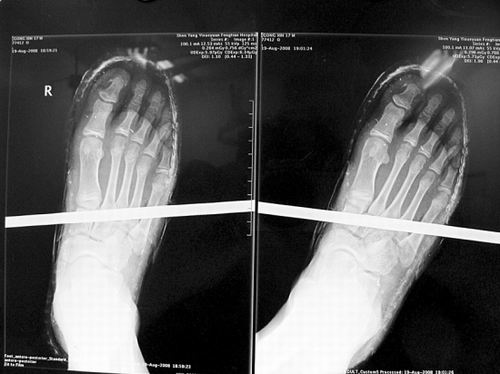

X光片顯示無大礙

事發(fā)時(shí)男孩穿著一雙布鞋,骨外二科陳賓醫(yī)生操起剪刀,將布鞋一塊塊剪掉。經(jīng)X光透視,醫(yī)生驚奇地發(fā)現(xiàn):男孩雖然被鋼筋穿透了右腳,但骨頭、大的血管和神經(jīng)都沒受任何傷害!

20日,記者從X光片子上看到,鋼筋避開了男孩腳掌骨頭密集的部位,而是從腳弓處穿過,這個(gè)部位基本上以軟組織為主!罢鏇]想到,太神奇了!”幾名醫(yī)生連聲感嘆,術(shù)中,他們分工合作,小心翼翼地將鋼筋取出,并做了引流、清創(chuàng)、包扎。